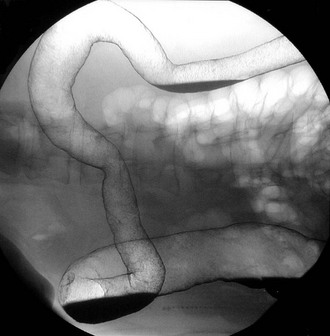

Colonoscopy enables a histological diagnosis to be obtained in colonic disease, and also allows biopsies of terminal ileum to be taken, which are often diagnostic. Barium ‘follow-through’ is the traditional method of examining small bowel but better images are sometimes obtained by controlled instillation of barium into the duodenum via a nasogastric tube. Typical radiological appearances of Crohn's disease include narrowing of the lumen due to mural oedema and fibrosis, nodularity and cobblestoning of the mucosal surface, deep fissured ulceration extending into the muscular wall, spiky ‘rose thorn’ ulcers and possibly evidence of fistula formation. Radiological changes in small and large bowel are shown in Figures 28.9 and 28.10. Note that large bowel abnormalities on barium enema may be difficult or impossible to distinguish from ulcerative colitis.